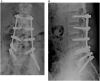

Case presentation: A 26-year-old male who suffered L4-5 fracture dislocation and some hemorrhage in pelvic cavity following a motorcycle accident. He had a median sacral artery injury, and we tried to the trans-catheter arterial embolization, however it could not be success. The embolization was performed using of gelatin sponges in bilateral internal iliac artery and left 4th lumber artery. After his admission, a demand of transfusions lasted for 7 days.